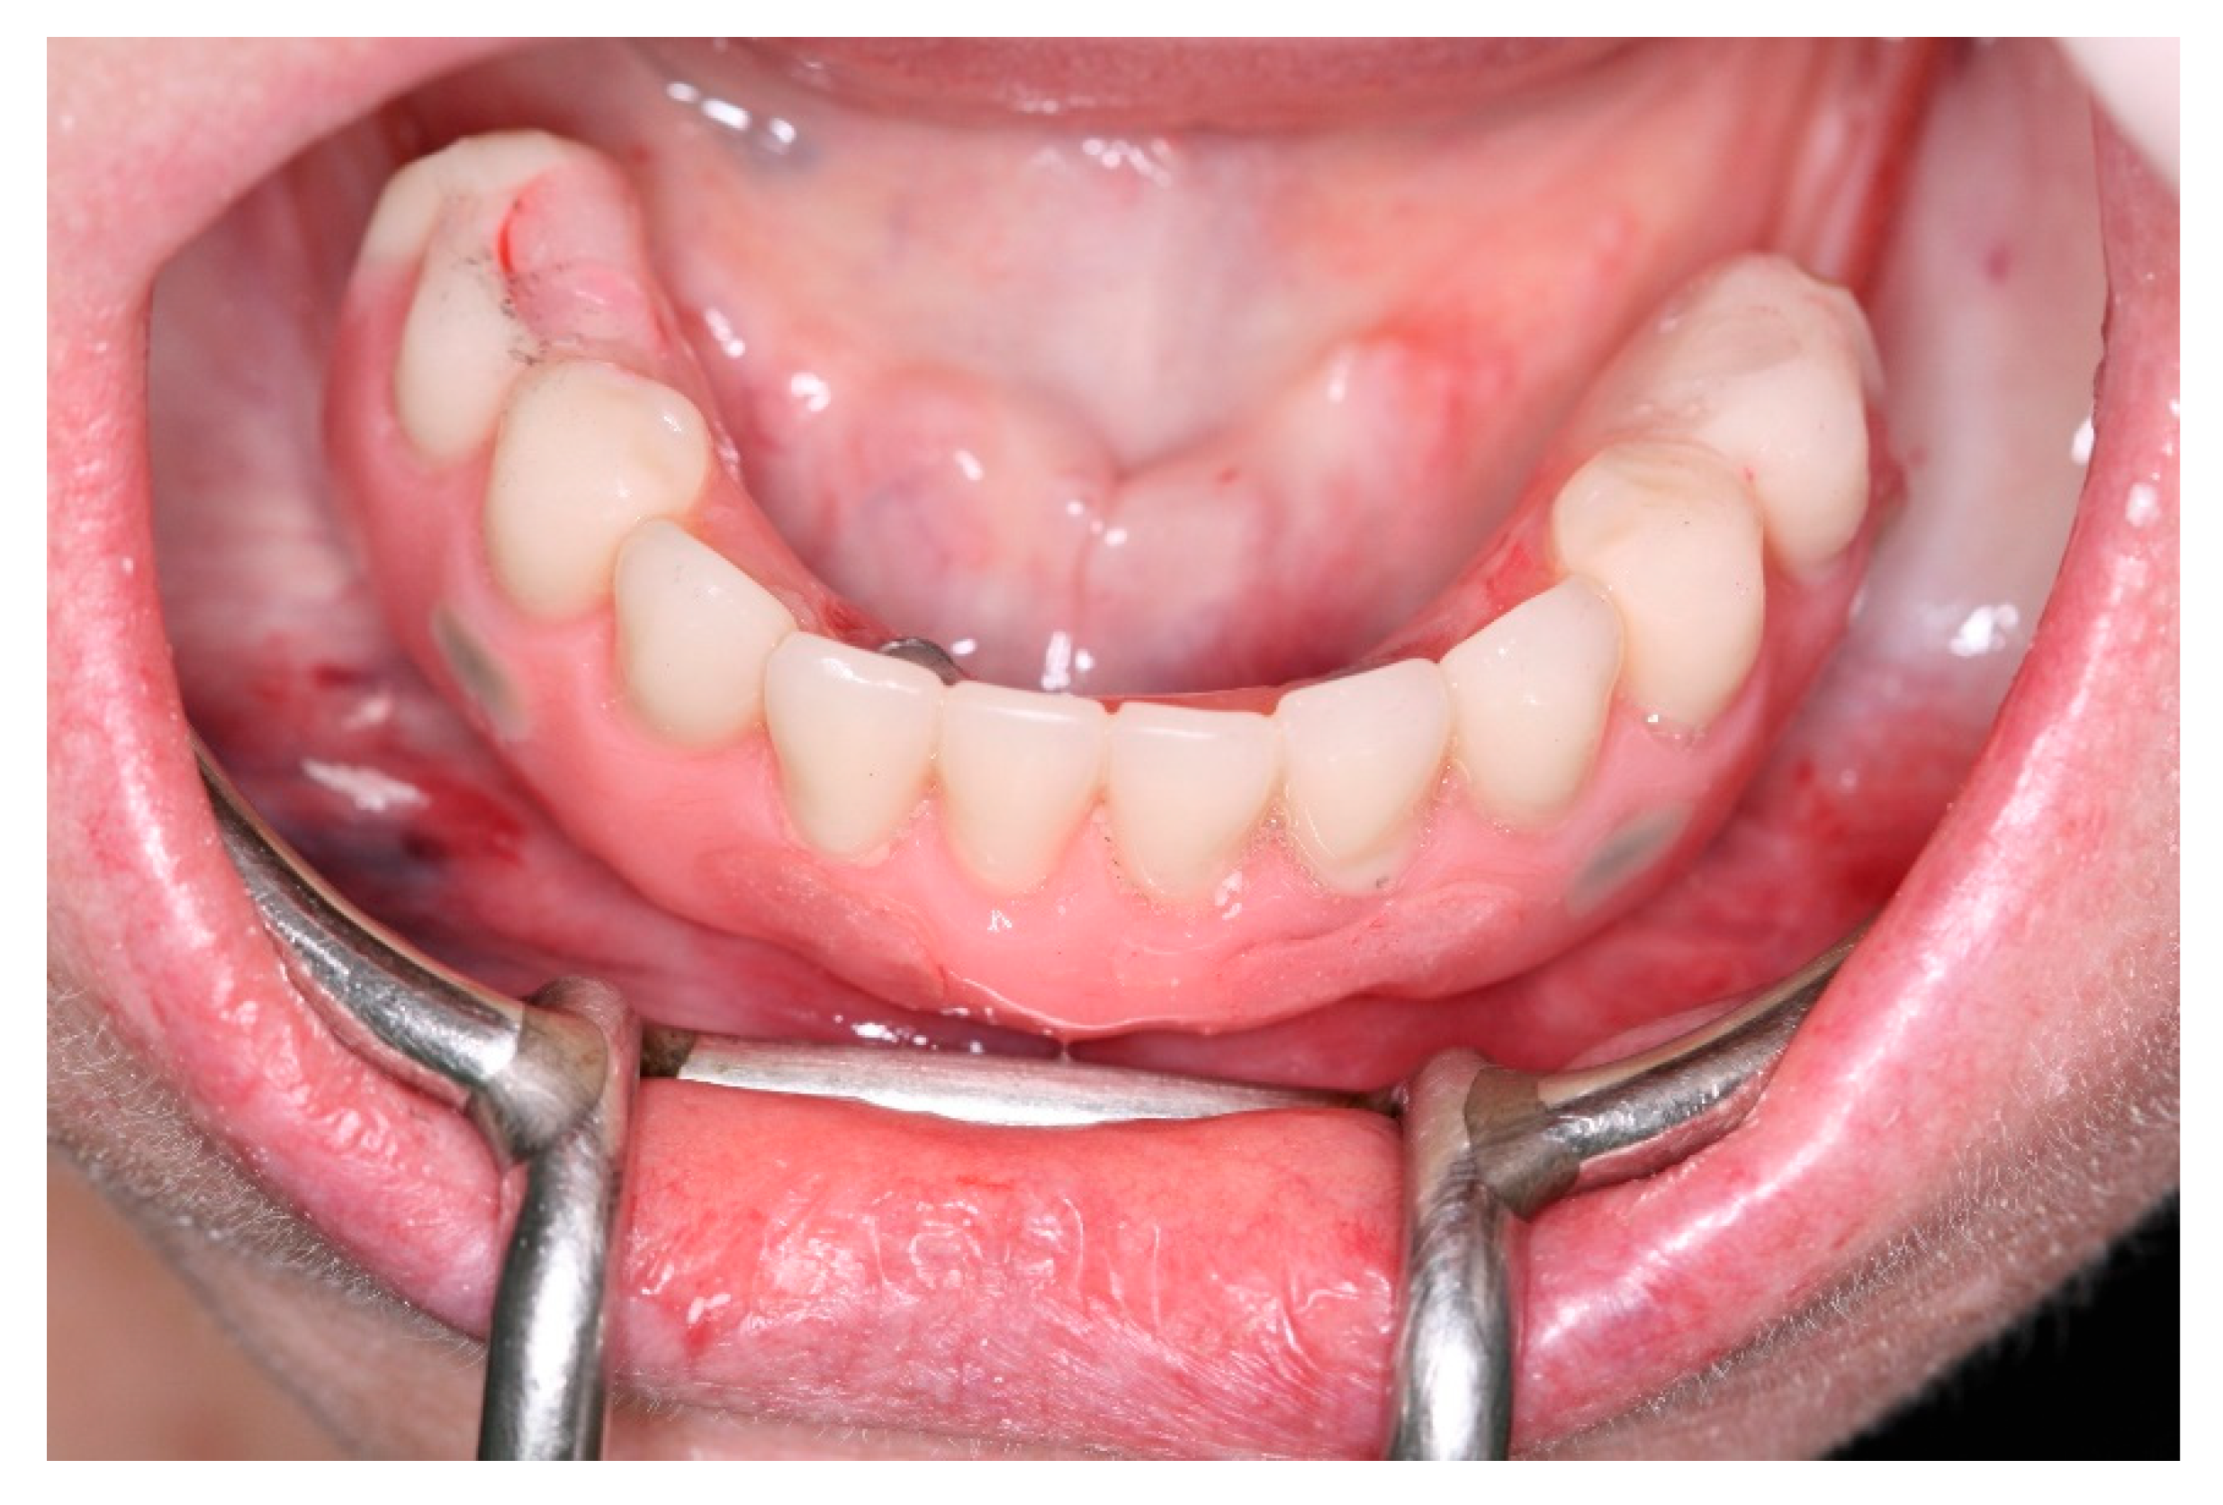

Figure 21. Buccal view of the new fixed screw-retained full-arch rehabilitation in occlusion.

After a healing period of 3 months the patient returned to change que temporary fixed prothesis for a new one, more delicate and with a reinforced metallic bar for a better ferulization of the implants and better dissipation of the stress during function. After removal of the temporary prosthesis we could see the peri-implant mucosa was healthy (Figure 19), without bleeding on probe nor peri-implant sulcus with more than 3mm depth, even around the implants were there were lack of a satisfactory keratinized tissue band, showing us that the patient was being able to maintain the cleansing of the region below the prosthesis. A new fixed rehabilitation over the implants was produced (Figure 20, Figure 21 and Figure 22). 2 years after the surgery we could see on a control panoramic radiograph no signs of bone remodeling above the expected around the implants (Figure 23).